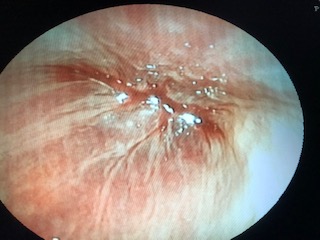

Ⅴ.内視鏡検査(胃カメラ)

- 犬猫用よりも細径の内視鏡を亀専用として使用

- 消化管の検査や胃内異物の摘出などに使用

鎮静下での検査となります

症例:繰り返す吐血 炎症・出血部位を認め、病理検査